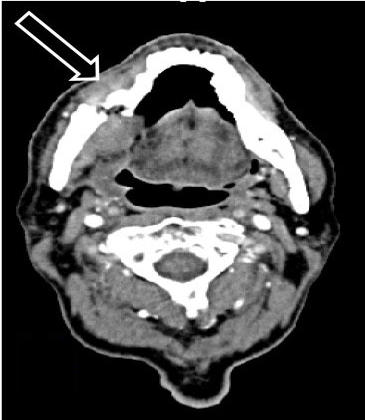

Imagen de tomografía computarizada (TC) de osteonecrosis de maxilar inferior (mandíbula) con una flecha que indica una fractura.

Fuente: West J Emerg Med. Jan 2015. doi: 10.5811/westjem.2014.10.23837. CC BY 4.0